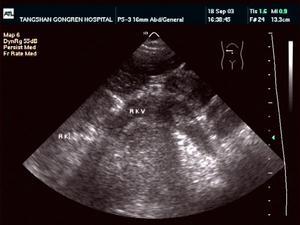

白色的箭頭指示腎靜脈血栓腎靜脈血栓的常見原因包括兩類疾病:一是血液高凝狀態,常見引起血液高凝狀態的疾病有腎病綜合徵;嬰幼兒嚴重脫水;妊娠或口服避孕藥;先天性血栓症如先天性抗凝血酶Ⅲ缺乏,先天性蛋白C缺乏症等;系統性紅斑狼瘡骨髓纖維增生症等二是靜脈壁受損常見引起靜脈壁受損的疾病有腎細胞癌侵犯腎靜脈;腎臟外傷;鄰近器官組織病變壓迫腎靜脈,如腫大淋巴結,腹主動脈瘤等

1.影像學檢查無創的影像學檢查如B超CT、磁共振及腎核素掃描等,只對腎靜脈主幹血栓有診斷意義。典型的徵象為擴大的腎靜脈內見到低密度的血栓,病腎周圍靜脈呈現蜘蛛網狀側支循環對腎靜脈分支血栓診斷價值不大。